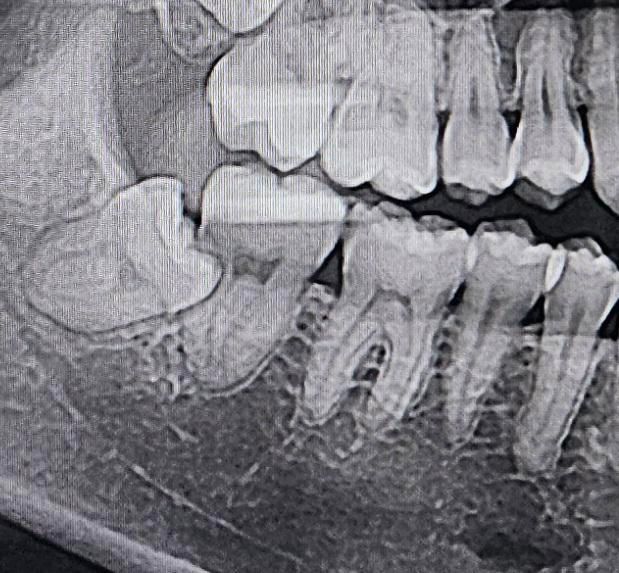

이 사랑니 발치하려면 어금니까지 발치해야할까요?

안녕하세요. 어금니 쪽 잇몸이 욱씬거려서 치과에 갔더니 사랑니 때문인것 같다고, 사랑니 발치하려면 어금니도 같이 발치해야할 것 같다는데 진짜 그래야 할까요?ㅠ 사랑니 전문 병원에 가면 사랑니만 뽑을 수도 있을까요? 난이도가 높은 사랑니인지 궁금합니다. 충치는 전혀 없습니다.

정확한건 CT도 찍어보고 사랑니 발치후에 앞치아를 확인해보셔야되겟지만 엑스레이 사진만봐서는 앞치아도 발치를 해야될수도 있습니다.

사랑니 전문 치과는 가보시되 현재 사진은 중첩된 부분이 있어 발치 후에 다시 평가를 해봐야 할 것 같습니다.

사랑니가 매우 깊게 있으며 앞의 치아와도 간섭이 심해 보입니다.

난이도가 높은 발치일것으로 생각되나 발치가 불가능한것은 아닙니다.

구강외과 전문의 선생님이 있는 병원에서 발치를 하는것을 권유드립니다.

현재 매복사랑니가 기울어져서 앞의 어금니 뿌리도 손상되어 있기에 두가지 치아 모두 발치가 필요로 되는 상황입니다. 현재 난이도가 높은 발치로 매복 사랑니 발치경험이 풍부한 구강외과 전문의에게 치료를 받길 권합니다.